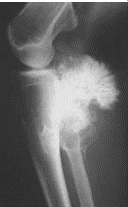

Osteosarcoma

malignant tumor of neoplastic mesenchymal cells synthesizing osteoid or immature bone

second decade; distal femur and proximal tibia, proximal humerus